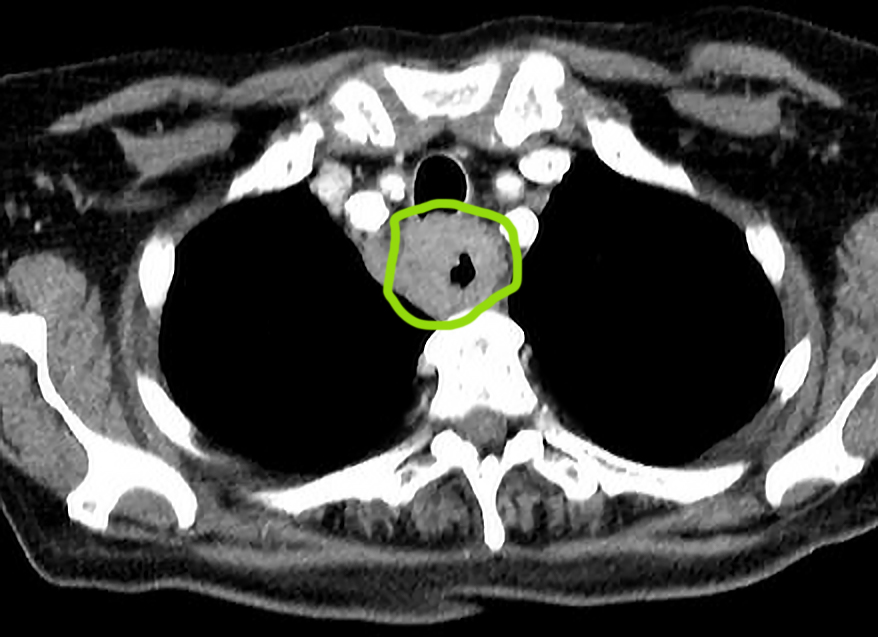

CT scan - esohageal cancer

Cancer of the esophagus may distort and block the esophagus and invade surrounding structures.